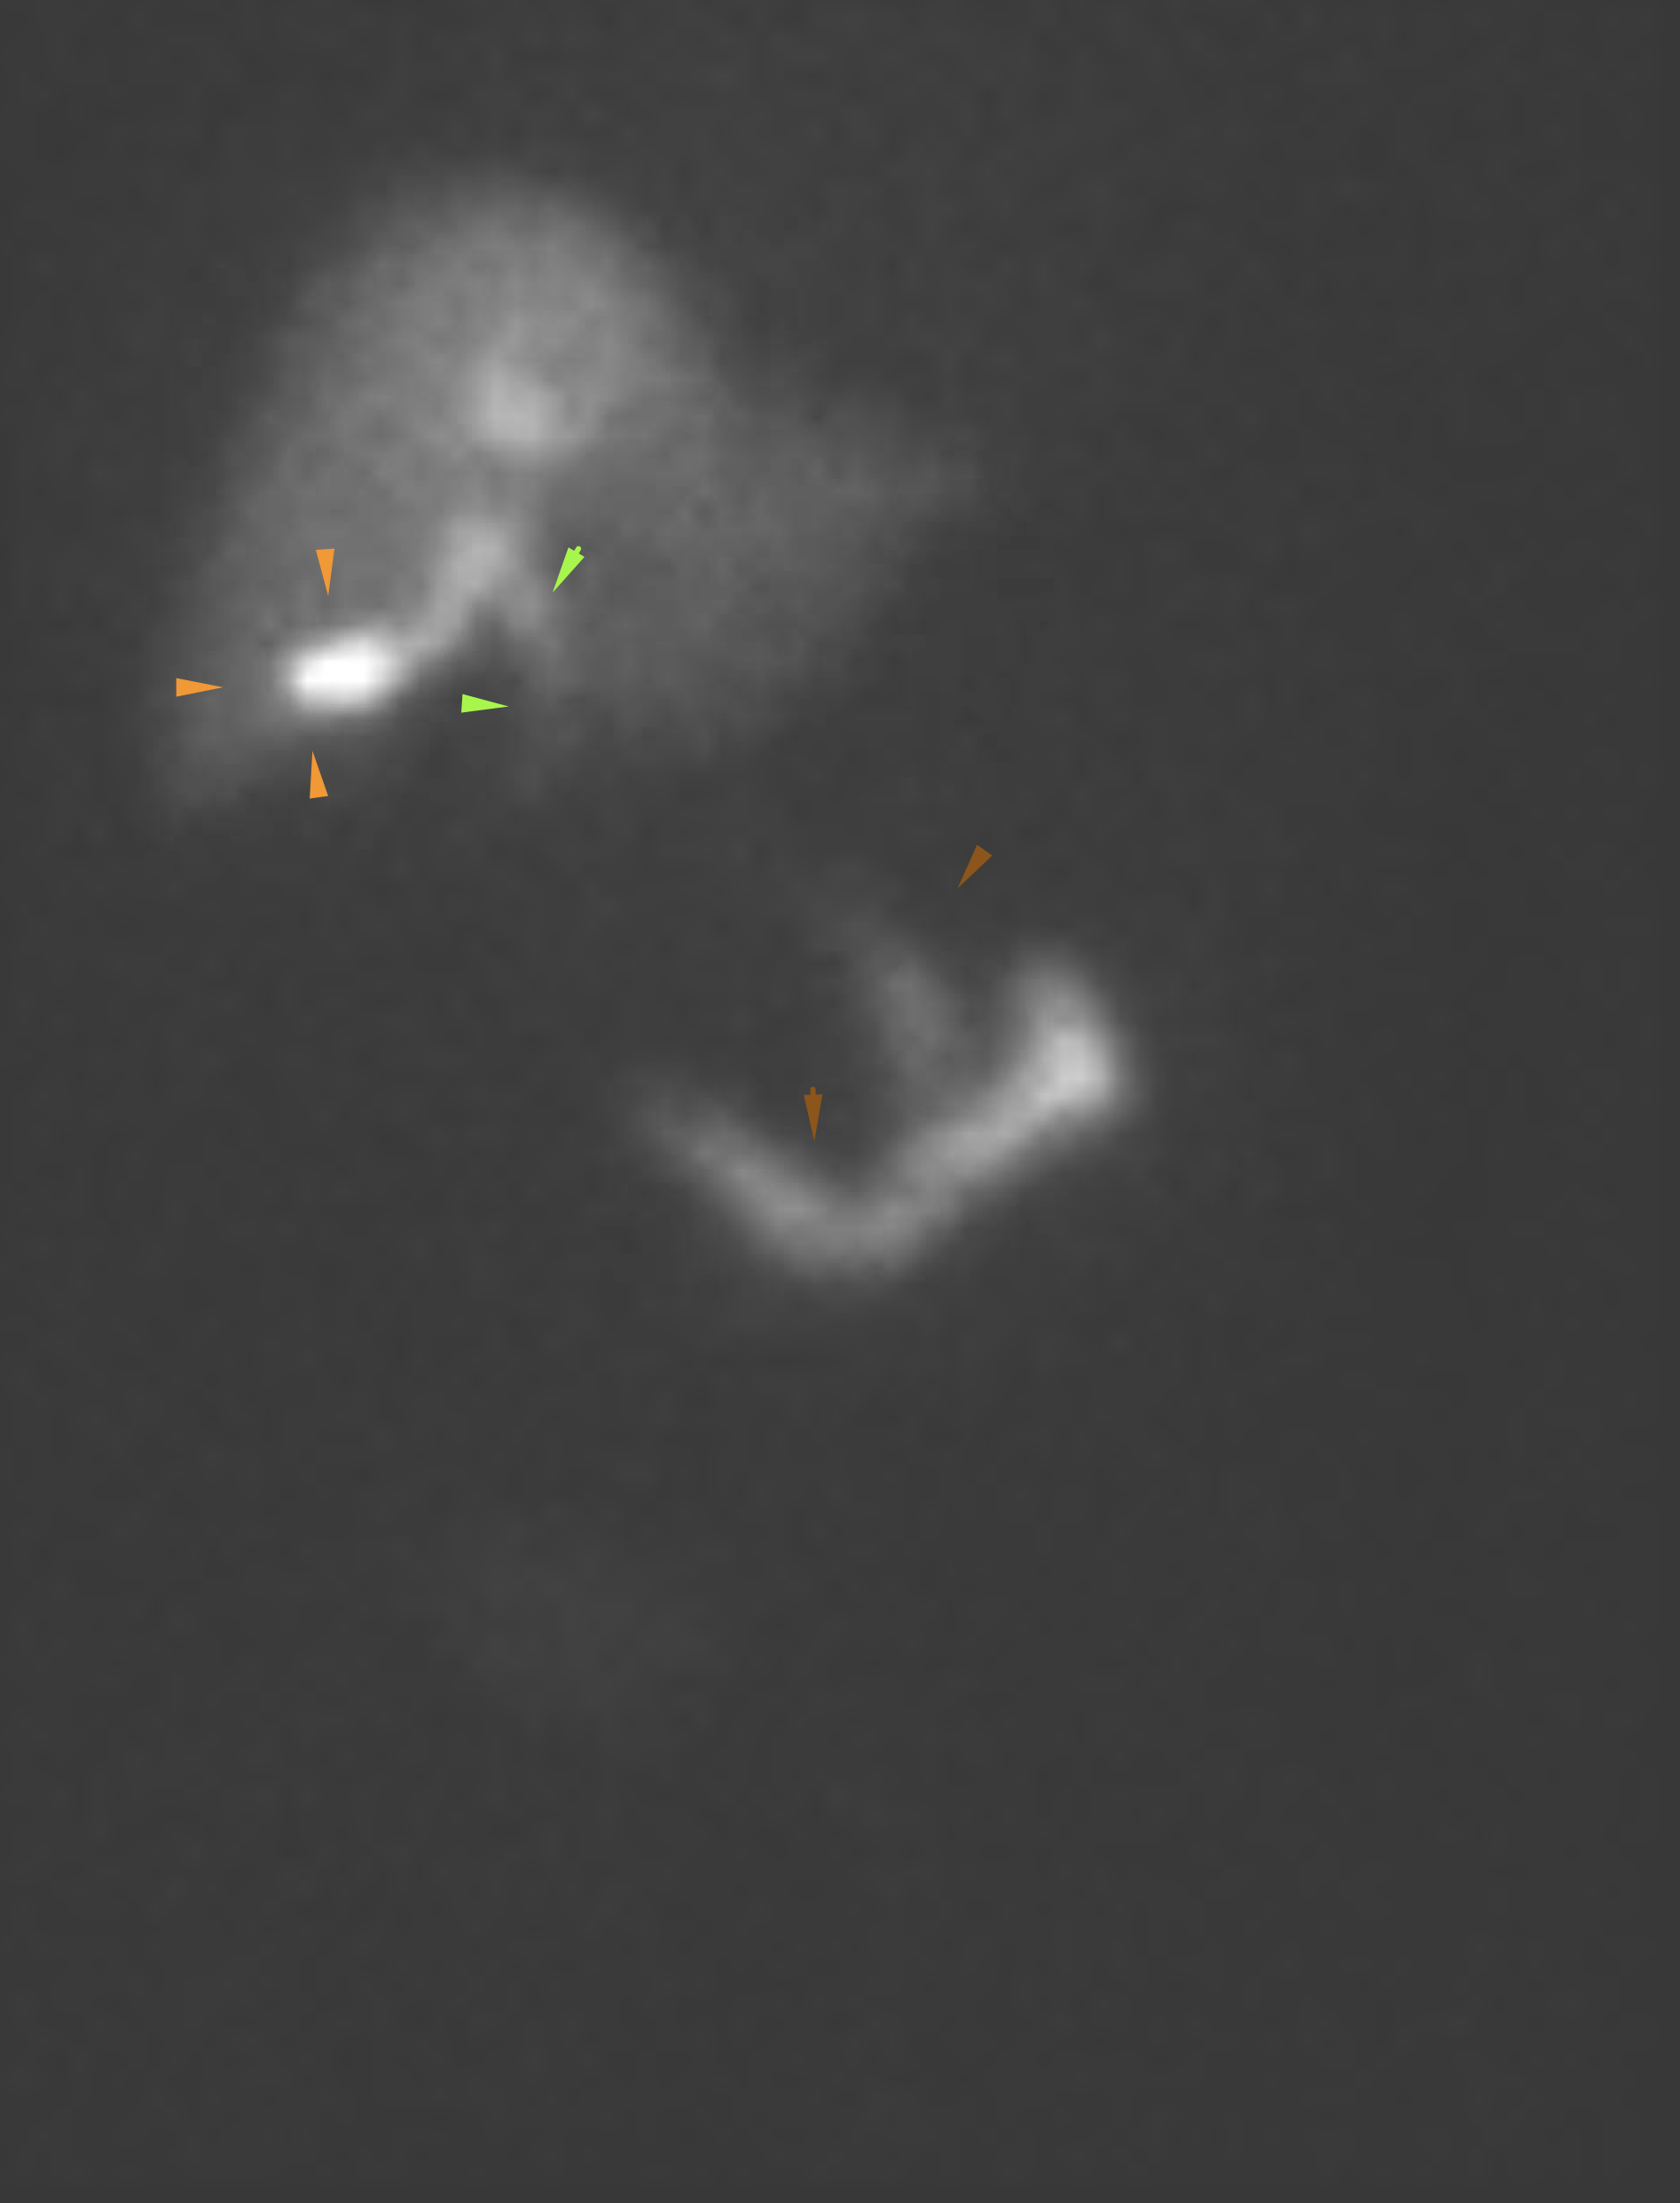

Age: 78

Sex: Female

Indication: Right upper quadrant pain

Radiotracer: Tc99m mebrofenin

Sample ReportNo evidence for acute cholecystitis. Patent biliary system.